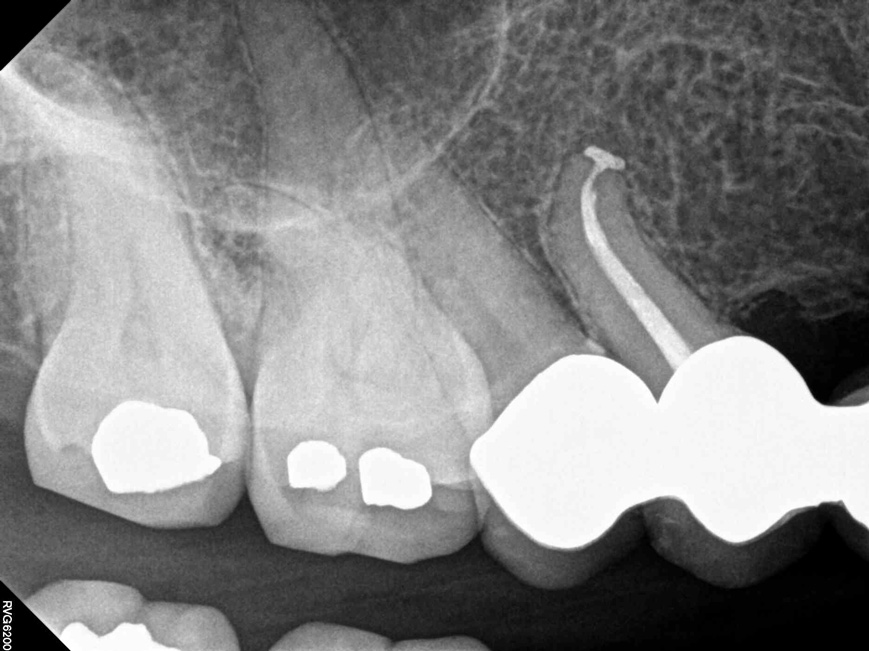

Fig 4.  Due to reported allergies to resin-based materials and eugenol, obturation was completed with a calcium hydroxide-based sealer (Figure 4 and Figure 5) with healing noted at a 1-year follow-up (Figure 6).

Figure 4

Fig 5.  Due to reported allergies to resin-based materials and eugenol, obturation was completed with a calcium hydroxide-based sealer (Figure 4 and Figure 5) with healing noted at a 1-year follow-up (Figure 6).

Figure 5

Fig 6.  Due to reported allergies to resin-based materials and eugenol, obturation was completed with a calcium hydroxide-based sealer (Figure 4 and Figure 5) with healing noted at a 1-year follow-up (Figure 6).

Figure 6

Due to reported sensitivities by patients to certain materials, the use of alternative materials does occasionally become necessary.  The endodontic literature demonstrates the safety and efficacy of calcium hydroxide-based sealers, and consequently these represent a suitable alternative (Figure 4 through Figure 6).